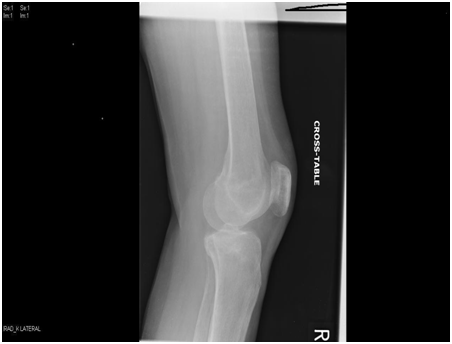

We present a 77 years old Caucasian female with spontaneous onset of pain in both knees for several weeks before presenting to the casualty then to our fracture clinic. There was no history of trauma. The patient is known to have Rheumatoid arthritis (RA) for over 30 years and has been on Bisphosphonate treatment (Alendronate) for over 24 months following the diagnosis of osteoporosis by DEXA scan. Plain radiographs showed subtle linear areas of sclerosis bilaterally in her proximal tibiae (Figure 1 & 2). Magnetic resonance imaging confirmed the presence of extra-articular linear high signal intensity change on T1, T2 with surrounding marrow edema consistent with insufficiency fractures in these areas as well as her right distal femur (Figure 3). These fractures were treated successfully with activity modification and weight bearing in a hinge knee brace as symptoms allows for six weeks along with physiotherapy input. Alendronate was stopped and Teriparatide (Recombinant PTH) was started.

Figure 2 AP & lateral radiograph of the right tibia and distal femur showing an insufficiency fracture with osteosclerotic changes at the medial proximal tibia and distal femur.